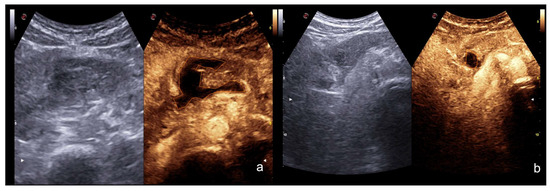

“Turn on the light”: CEUS is more sensitive than US for the detection of solid organ injuries (Figure 23).

Figure 23.

Sub-Glissonian hepatic hematoma in a 40−year-old woman. At B-mode US study (a,b, split image on the left), no definite hematomas was showed. At CEUS evaluation (a,b, split image on the right), the presence of a small sub-Glissonian hematoma was clearly delineated (arrow). Contrast-enhanced CT examination (c, axial and d, coronal view) confirmed the presence of the small non-bleeding sub-Glissonian hematoma (arrow).